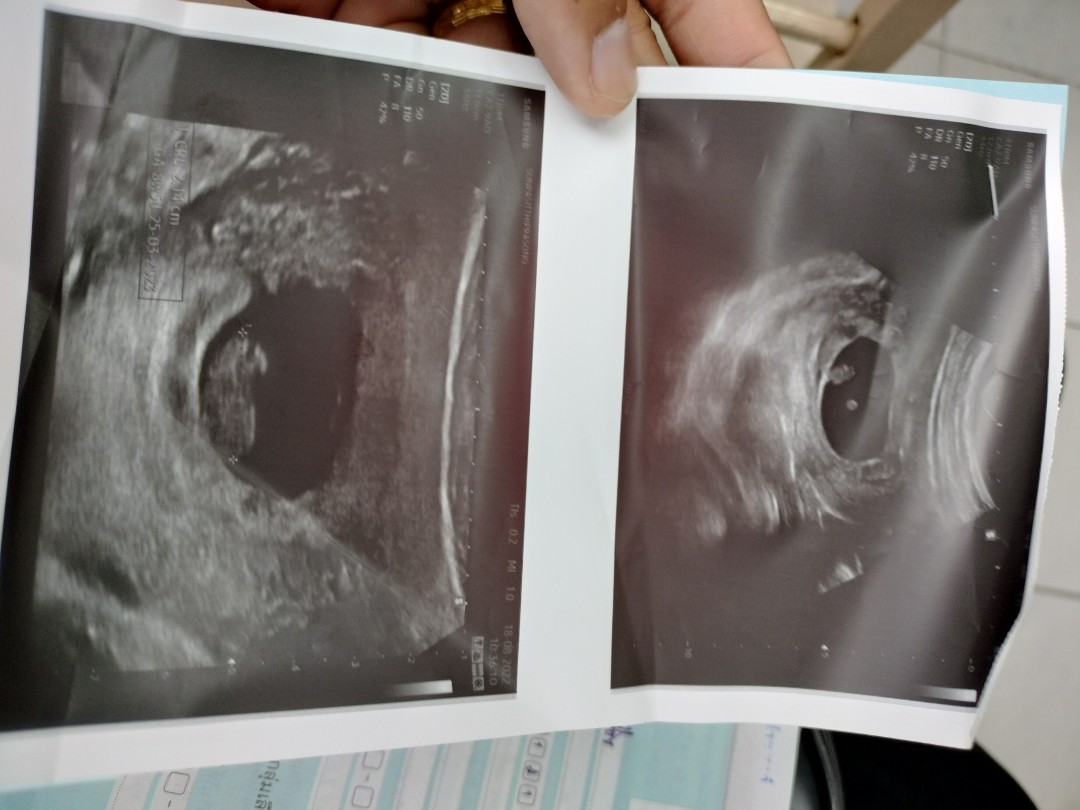

ในที่สุดก็เจอน้องพร้อมเสียงหัวใจคะ❤️❤️

เจอน้องแล้วจ้าา💗